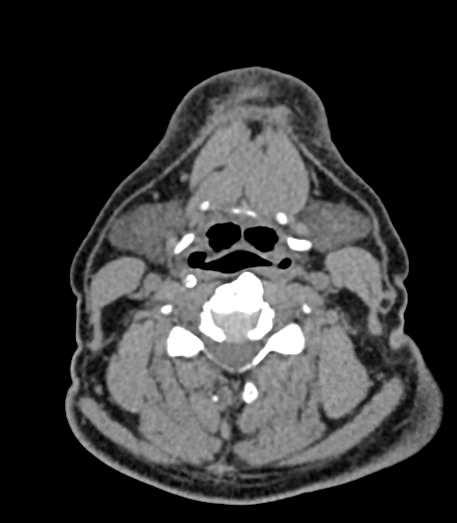

Используемые в нашей клинике томографы, благодаря своему оснащению, позволяют получать снимки высокого качества и детализации за короткий промежуток времени, что минимизирует уровень лучевой нагрузки на организм. Используя полученные данные, аппараты создают трехмерные реконструкции анатомической зоны. Это дает возможность наглядно оценить пространственное соотношение лимфатических узлов и близлежащих органов, выявить прорастание в окружающие ткани, особенно при образовании цепочек, пакетов и конгломератов лимфоузлов.

Для повышения качества визуализации лимфоузлов, особенно при подозрении на онкологических процесс, исследование проводится с внутривенным болюсным контрастированием. Контрастный препарат, содержащий йод, вводится в вену с помощью автоматического шприца. Распространяясь по сосудистой системе, препарат накапливается в патологических очагах, в том числе, в измененных лимфоузлах, и увеличивает их яркость на КТ-изображениях. Методика контрастирования помогает выявлять опухоли минимальных размеров, проводить дифференциальную диагностику между доброкачественными и злокачественными новообразованиями и воспалительными изменениями.

Мультиспиральная КТ позволяет оценить размеры лимфатических узлов, выявить деформацию их контуров, неоднородность структуры, установить точную локализацию, взаимодействие с близлежащими органами и окружающими тканями, обнаружить инфильтрацию прилегающих структур.